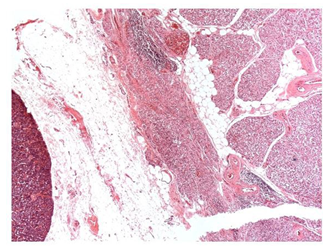

La tiroides mostró una severa atrofia folicular generalizada, folículos reducidos de tamaño e irregulares, la mayoría perdieron el coloide o permanecieron con escaso coloide condensado, áreas de infiltración de tejido adiposo en el intersticio (Figuras 4 y 5), múltiples focos de infiltrado de linfocitos y células plasmáticas, con predominio de los primeros, cambios ateroscleróticos en vasos arteriolares.

Figura 4 Tiroides. Se observa infiltración moderada de tejido adiposo entre los lobulillos, además de focos de inflamación linfoplasmocitaria (40X, H&E).